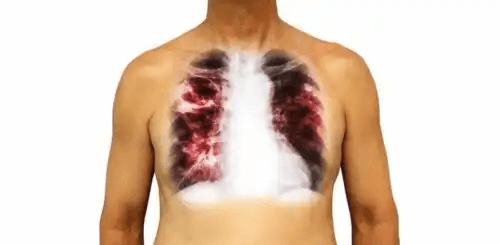

1. Lunginflammation

Detta är en bakteriell infektion främst orsakad av Streptococcus pneumonia. Inledningsvis påverkar lunginflammation lungparenkymet. Men när sjukdomen går vidare till sina allvarligare stadier kan den spridas från lungorna till blodet.

För att behandla denna sjukdom kommer din läkare vanligtvis att skriva ut antibiotika. Riktlinjerna du får kommer att vara direkt relaterade till just dina samt sjukdomens egenskaper. Alla former av lunginflammation har inte samma förlopp eller symptom.